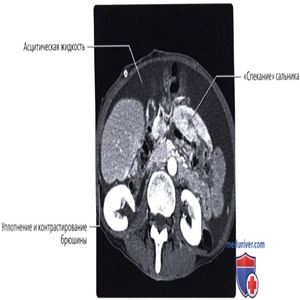

МРТ, постконтрастное Т1-ВИ, режим подавления сигнала от жира, аксиальный срез: у пациента с перфоративным аппендицитом определяются признаки перитонита с уплотнением и контрастированием брюшины и крупными инкапсулированными скоплениями асцитической жидкости. У здоровых пациентов брюшина не должна визуализироваться, она обычно видна только при уплотнении вследствие инфекции, воспаления или опухоли.

КТ с контрастированием, аксиальный срез: у пациента с сепсисом после хирургического вмешательства определяется выраженное накопление контрастного вещества брюшиной и ее уплотнение в сочетании с инкапсулированным скоплением жидкости по ходу края печени.